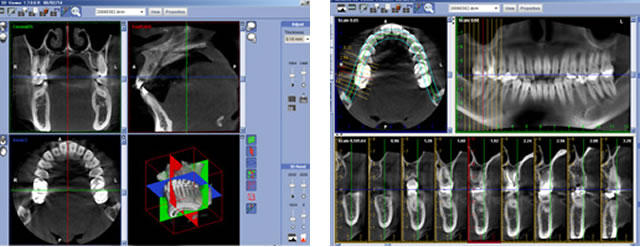

そのため、CTを駆使して歯や骨の状態を細かく確認し、治療内容や治療期間、費用につきましてもしっかりとご説明いたします。